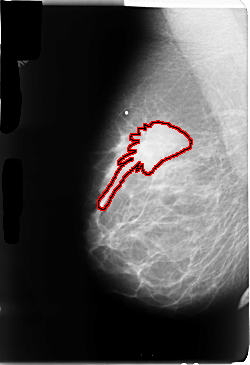

FILE: B_3051_1.RIGHT_MLO.OVERLAY

TOTAL_ABNORMALITIES 1

ABNORMALITY 1

LESION_TYPE MASS SHAPE IRREGULAR-ARCHITECTURAL_DISTORTION MARGINS OBSCURED-ILL_DEFINED-SPICULATED

ASSESSMENT 4

SUBTLETY 3

PATHOLOGY MALIGNANT

TOTAL_OUTLINES 1

BOUNDARY

RIGHT_MLO LINES 4736 PIXELS_PER_LINE 3240 BITS_PER_PIXEL 12 RESOLUTION 50 OVERLAY